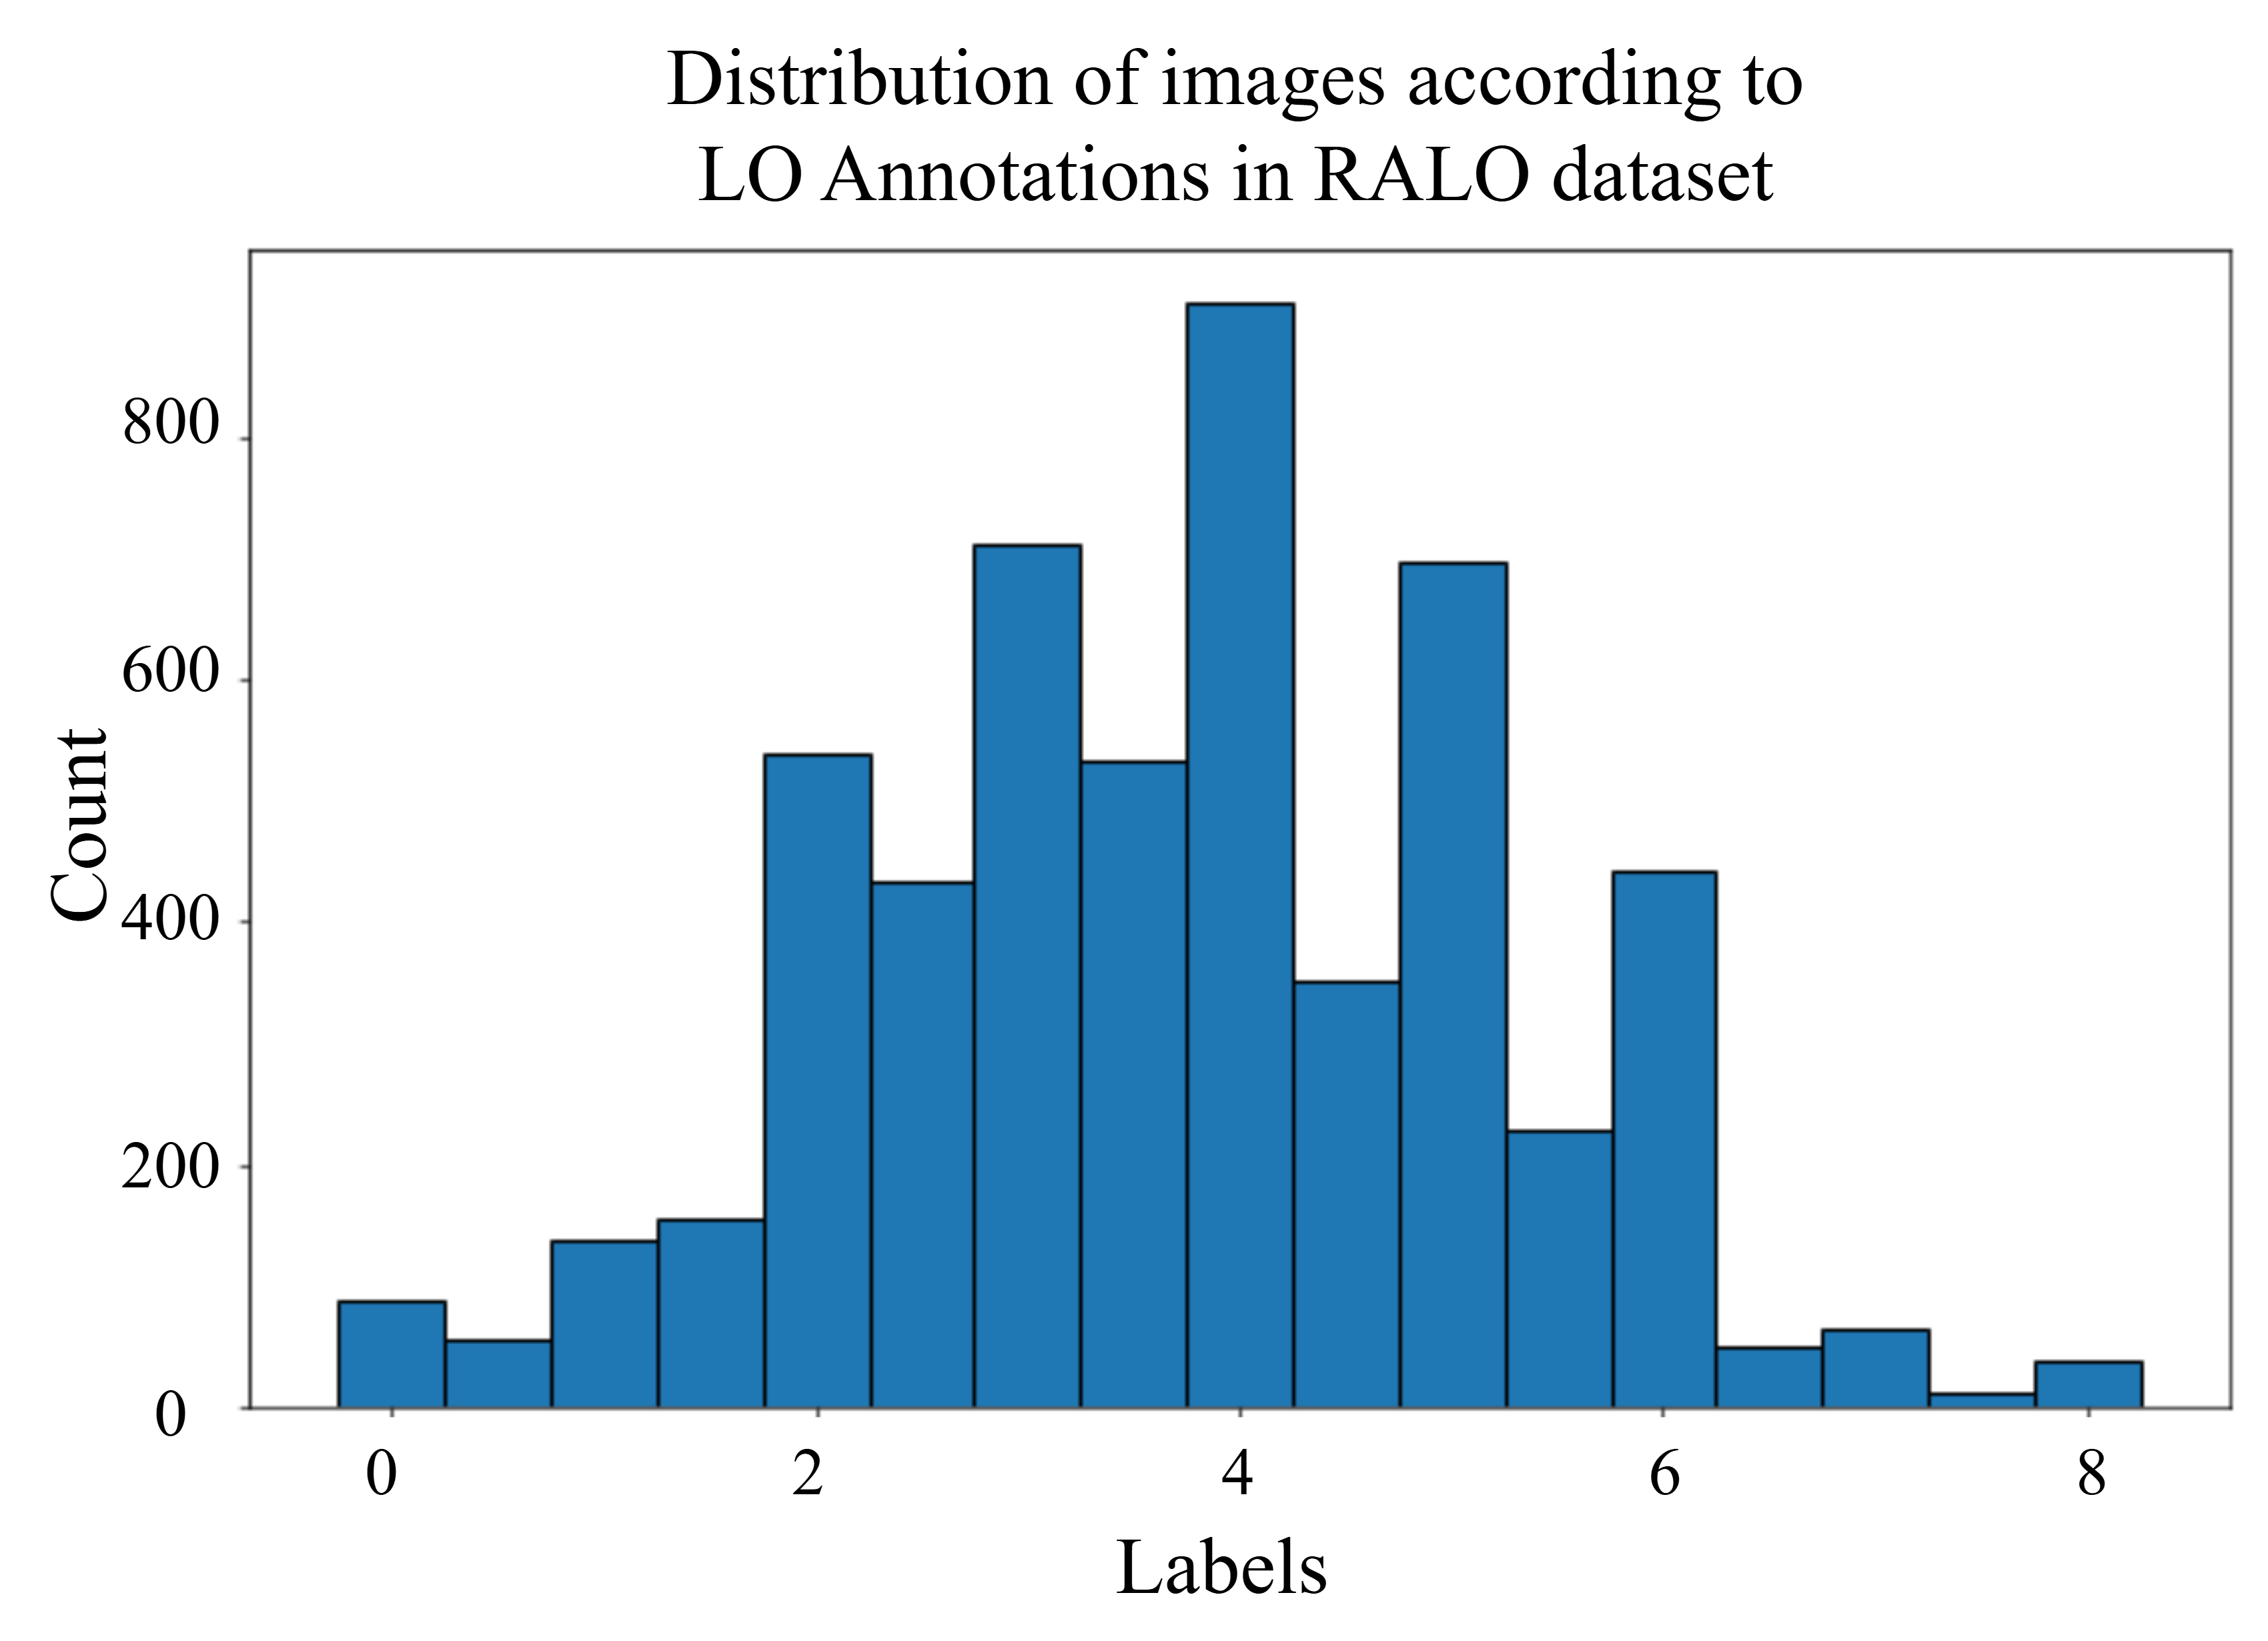

The primary goal of this research is to evaluate the effectiveness of deep learning models in determining the severity of lung diseases. To accomplish this, we utilized the Radiographic Assessment of Lung Opacity Score (RALO) dataset, which consists of 2,373 chest X-ray images [16]. These images were carefully evaluated and scored by two expert radiologists from Stony Brook Medicine to create a detailed COVID-19 dataset for research purposes. The dataset is divided into a training set of 1,878 images and a test set of 495 images. In this study, radiological grading focuses on two key criteria: Geographic Extent (GE) and Lung Opacity (LO). GE refers to the spread of lung involvement by ground-glass opacity or consolidation, with separate scores for the right and left lungs. The GE score ranges from 0 (no consolidation) to 4 (maximum consolidation), and the overall GE score is the sum of the left and right lung scores. LO is assessed independently for each lung, with scores ranging from 0 (no opacity) to 4 (total whiteout), reflecting varying degrees of lung opacity. The total LO score, which ranges from 0 to 8 points, is calculated by summing the scores of both lungs. The final ground-truth scores are averages of the two radiologists’ evaluations, and they are represented in the set [53]. An offline combined lung and score replacement is applied to the training set as done in a previous work [42]. The resultant dataset is distributed as shown in Figure 4.

In this context, the threshold values used for applying Conditional TransMix are chosen according to the initial distribution of the labels across the dataset. Figure 4 illustrates the distribution of GE scores across the dataset, revealing that images with a score greater than 4 are more prevalent than those with a score of 4 or less. This imbalance suggests a natural division within the data, prompting us to use a score of 4 as a threshold. By setting this threshold, we effectively distinguish between cases with higher and lower severity, allowing for targeting the less frequent data with the proposed augmentation method. Similarly, for the LO scores, images with scores below 2 and above 6 are less frequent compared to those within the mid-range scores. This uneven distribution highlights the scarcity of cases with either very low or very high severity, which could pose challenges for the model’s training and evaluation. Understanding this distribution is crucial for applying the augmentation to the scarce data to ensure balanced representation and accurate predictions across all severity levels.